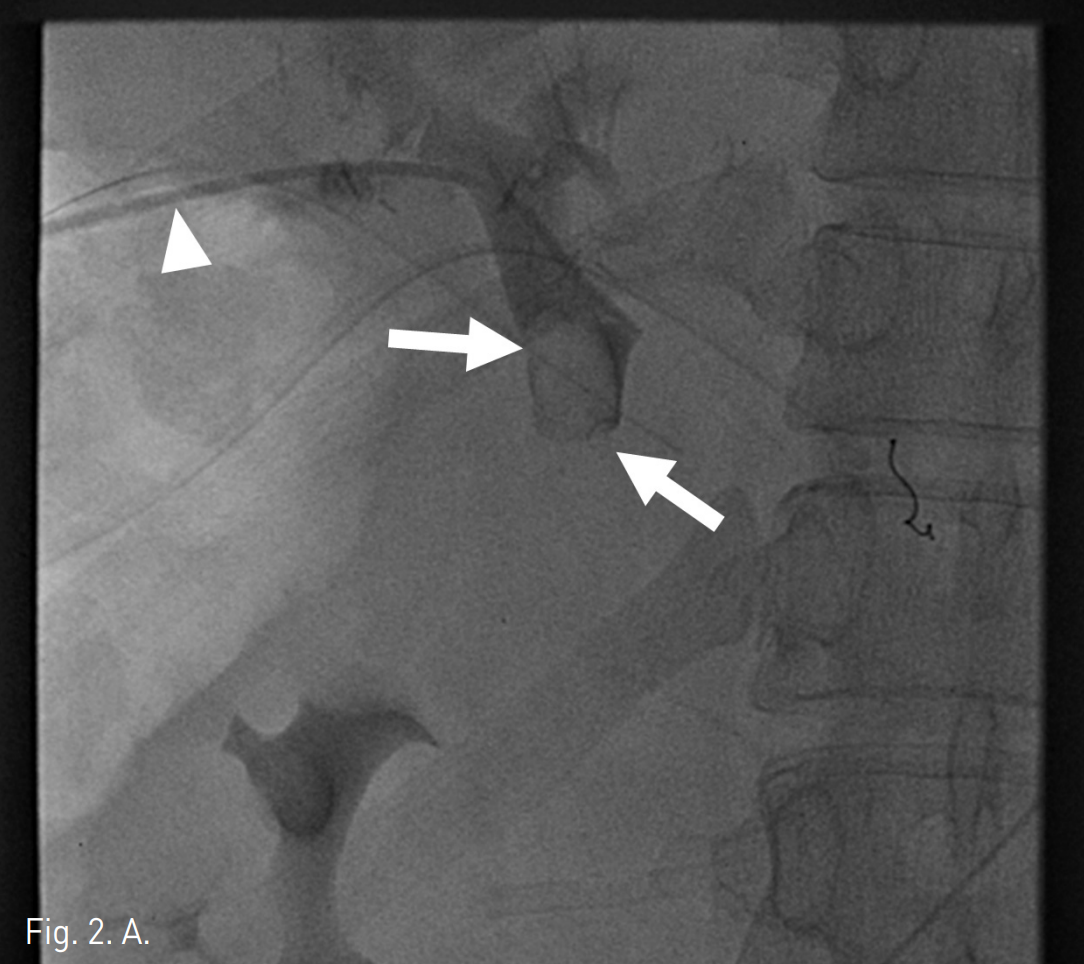

초음파 유도 하에서 우측 문맥을 20G Chiba needle을 이용해 직접 천자한 후 문맥 조영 영상에서 문맥부 합성혈관의 혈전성 폐색을 확인하였다(Fig. 2A). 5F Davis catheter (Cook, Bloomington, IN, USA)와 urokinase (200K unit)를 이용한 혈전용해술, 7F Sheath catheter (Cook, Bloomington, IN,USA)를 이용한 흡입 혈전제거술과 stent를 이용한 치료를 계획하였다. 혈전용해술 및 흡입 혈전제거술을 시행한 후 문맥의 혈류가 회복되었으나 이 과정에서 간 내 문맥(intrahepatic portal vein)에 혈전성 색전에 의한 것으로 보이는 간 내 문맥의 충만결손이 발생하였고(Fig. 2B), 이에 대해 다시 흡입혈전제거술을 시행하여 문맥의 흐름을 원활히 하였다. 이후 자가팽창형 스텐트(10mm x 80mm)(S&G biotech, Seoul, Korea)를 합성혈관의 근위부 및 원위부 접합부를 모두 포함하도록 설치하였다(Fig. 2C), 스텐트를 위치시킨 후 시행한 문맥조영술에서 간 내 문맥의 충만결손이 사라지고 스텐트 삽입 부위의 문맥의 혈류가 원활하며 출혈 등의 시술 후 부작용이 없음을 확인하고 시술을 종료하였다 (Fig. 2D).

A. Transhepatic approach (arrowhead) was used after puncturing a branch of patent right portal vein under US guidance Thrombotic occlusion of the synthetic graft portal vein was noted (arrows).